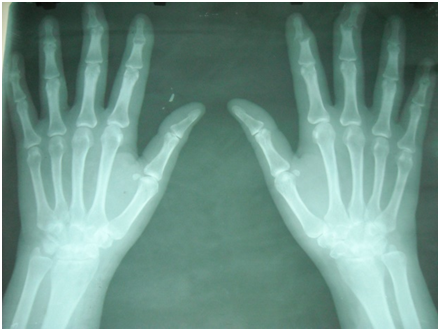

She denies fever, don't injure in skin, and she has never referred photosensibility.  They are indicated complementary;  As results a C Protein  is received it reactivates positive and to the Rx it is appreciated subluxation and cubital deviation of the 2nd and 3rd fingers of both hands with rupture sinovial and erosion signs in this fingers of the right hand with loss of the structure to articúlate (Figures 1 & 2).1-9

Figure 1&2  Subluxation and cubital deviation of the 2nd and 3rd fingers of both hands with rupture sinovial and erosion signs in this fingers of the right hand with loss of the structure to articúlate.